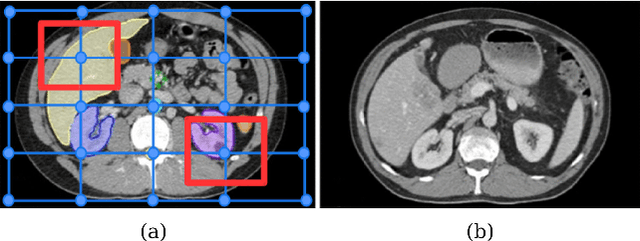

Abstract:Deformable registration has been one of the pillars of biomedical image computing. Conventional approaches refer to the definition of a similarity criterion that, once endowed with a deformation model and a smoothness constraint, determines the optimal transformation to align two given images. The definition of this metric function is among the most critical aspects of the registration process. We argue that incorporating semantic information (in the form of anatomical segmentation maps) into the registration process will further improve the accuracy of the results. In this paper, we propose a novel weakly supervised approach to learn domain specific aggregations of conventional metrics using anatomical segmentations. This combination is learned using latent structured support vector machines (LSSVM). The learned matching criterion is integrated within a metric free optimization framework based on graphical models, resulting in a multi-metric algorithm endowed with a spatially varying similarity metric function conditioned on the anatomical structures. We provide extensive evaluation on three different datasets of CT and MRI images, showing that learned multi-metric registration outperforms single-metric approaches based on conventional similarity measures.